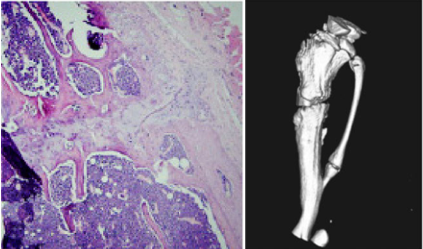

部分结果展示

HE staining ×100 micro-CT scanning